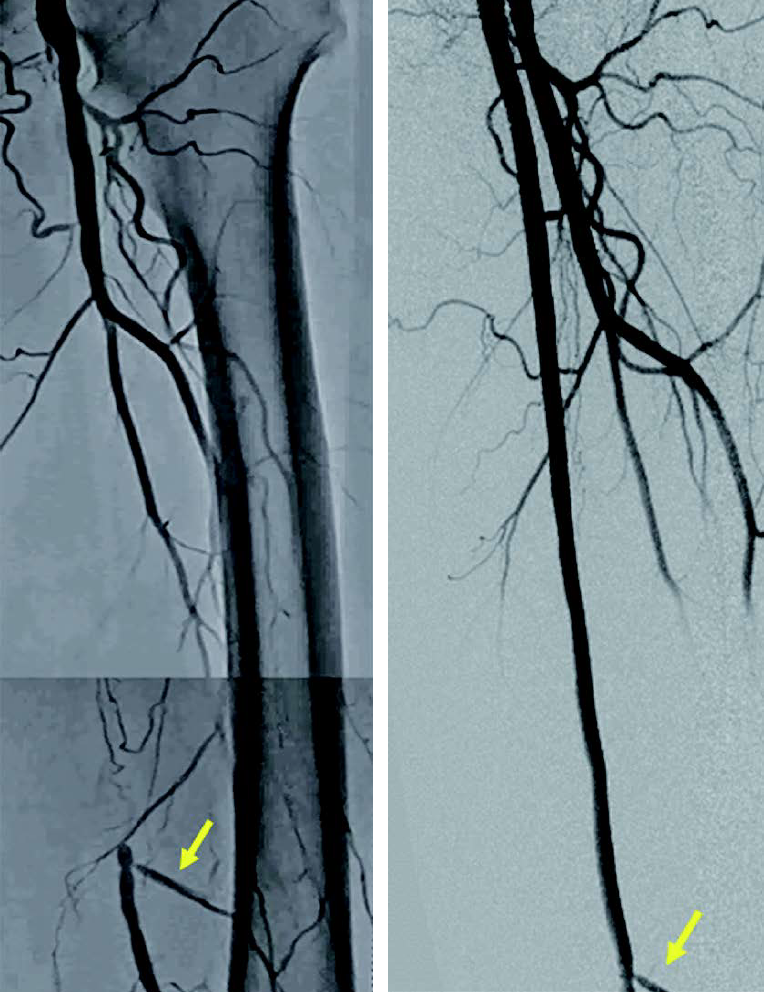

右浅大腿動脈閉塞(図3): 左鼠径部を穿刺(6 Fr シース)しcrossover後、順行性に0.014 inchマイクロカテーテルを使用して0.014 inch ガイドワイヤー(先端荷重1 g →3 g →40 g)を進めたが貫通できず、足背動脈を穿刺し逆行性に0.014 inch ガイドワイヤーを進め、貫通に成功。IVUS catheterで一部 subintimal trackingしていることを確認。5.0 mm 径バルーン(non-compliant balloon)で拡張後解離が生じ、末梢にバイアバーン® ステントグラフト5.0 × 150 mm、中枢に6.0 × 250 mm の2本を留置。病変の末梢には発達した2本の側副血行路を伴い、側副血行路の間に軽度狭窄病変を認めたため、中枢側の側副血行路をjailさせ、健常部にバイアバーン® ステントグラフトを留置。5.0 mm 径と6.0 mm 径バルーン(non-compliant balloon)で後拡張して終了。(図4)

両側浅大腿動脈閉塞病変に対してバイアバーン® ステントグラフトにて血行再建術を施行し、その後3年の経過において良好な経過をみている(図5)。側副血行路を温存するかどうかの議論はあるが、バイアバーン®ステントグラフトを健常部に留置し、遠位部に残存狭窄を残さないことが重要と考えている。さらに定期的な duplexでのフォローアップで、ステントedgeや中枢側の新規病変を早期発見し治療することが、ステント閉塞予防に不可欠と思い、実践している。最後に、長区域の浅大腿動脈病変の治療は、外科治療のオプションも見据え、血管外科医との連携は極めて重要と考えている。